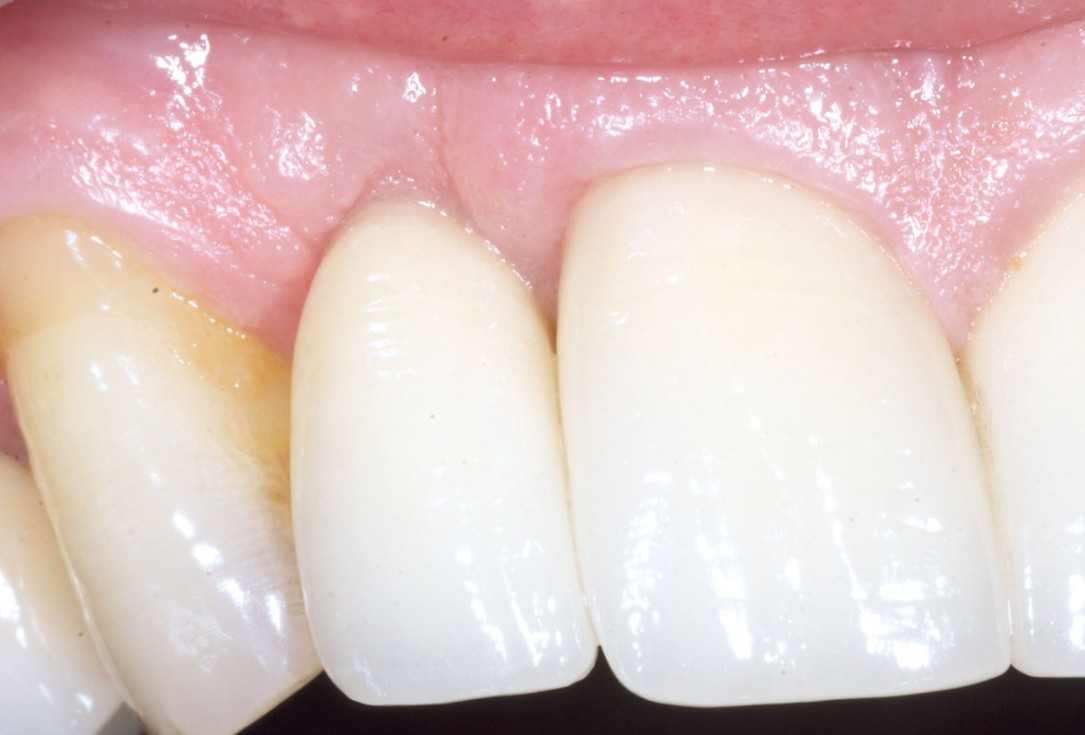

5/19 - 7 weeks after extraction of healing with a temporary tooth supported cantilever bridgeBone augementation with maxresorb® - Dr. R. Cutts